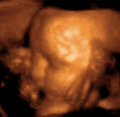

- متابعة وتصوير الجنين أثناء فترة الحمل.

| طب التوليد | Obstetrical sonography is commonly used during pregnancy to check on the development of the fetus. | انظر obstetric ultrasonography |